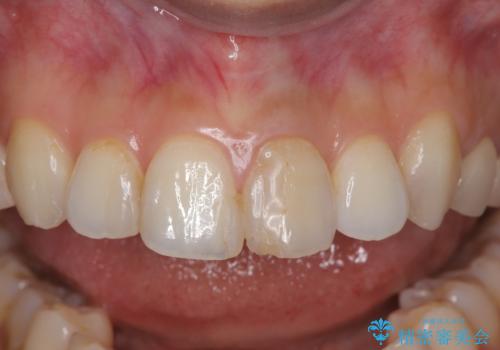

オールセラミッククラウンで治療を行い見た目の改善を行いました。

右上1もCRが入っており治療を勧めましたが、希望されず左上1のみ行いました。

色味は左上2に合わせたいとのご希望だったので、左上2に合わせています。